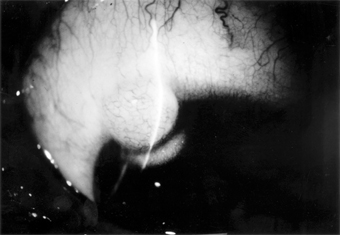

Malignant melanomas of the conjunctiva are rare. Most arise from areas of primary acquired melanosis; some arise from conjunctival nevi; a few apparently arise de novo from normal conjunctiva. Some are melanotic; others are heavily pigmented (Figure 5-29).

Figure 5-29

Figure 5-29: Conjunctival malignant melanoma.

Many tumors can be locally excised. More radical surgery (eg, exenteration of the orbit) does not usually improve the prognosis. The use of cryotherapy after excision of melanotic tumors may help to prevent recurrences.